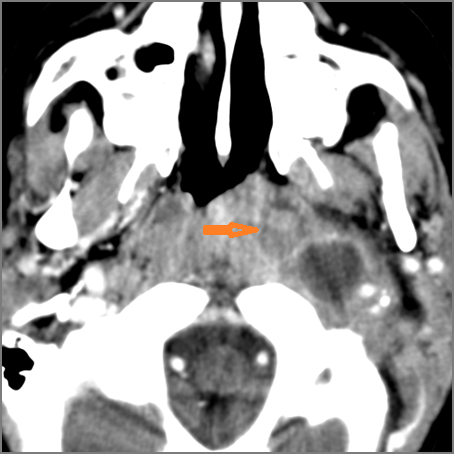

There is suppurative retropharyngeal lymphadenopathy. [Yes/No]

If there is suppurative retropharyngeal adenopathy what is the maximum short axis dimension of the largest suppurative node. MEASUREMENT [Yes/No]

There is related edema/abscess within the adjacent parapharyngeal/retropharyngeal spaces. [Yes/No]